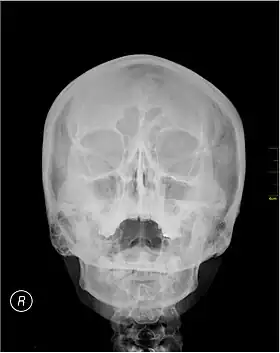

Waters' view (also known as the occipitomental view) is a radiographic view of the skull. It is commonly used to get a better view of the maxillary sinuses. An x-ray beam is angled at 45° to the orbitomeatal line. The rays pass from behind the head and are perpendicular to the radiographic plate. Another variation of the waters places the orbitomeatal line at a 37° angle to the image receptor. It is named after the American radiologist Charles Alexander Waters.

Waters' view can be used to best visualise a number of structures in the skull.

- Maxillary sinuses.

- Frontal sinuses, seen with an oblique view.

- Ethmoidal cells.

- Sphenoid sinus, seen through the open mouth.

- Odontoid process, where if it is just below the mentum, it confirms adequate extension of the head.